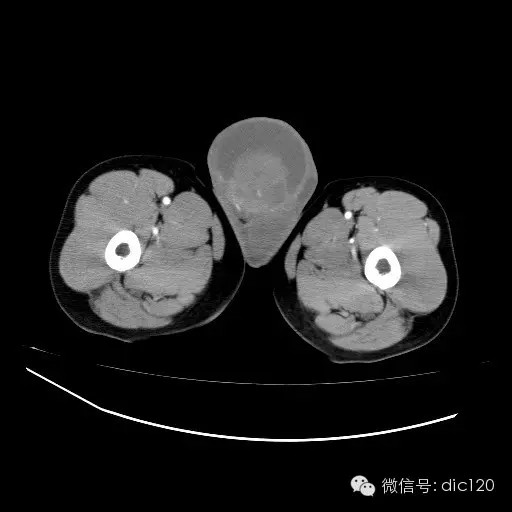

青年男性,右侧睾丸肿大,边界清晰,增强后睾丸不均匀中度强化,内可见多灶囊变坏死区,动脉期肿块内有细小动脉血管显示,延迟期可见分隔样强化,鞘膜囊可见积液。

定位定性:右侧睾丸恶性肿瘤。

【影像诊断】

右侧睾丸精原细胞瘤,右侧睾丸鞘膜积液。